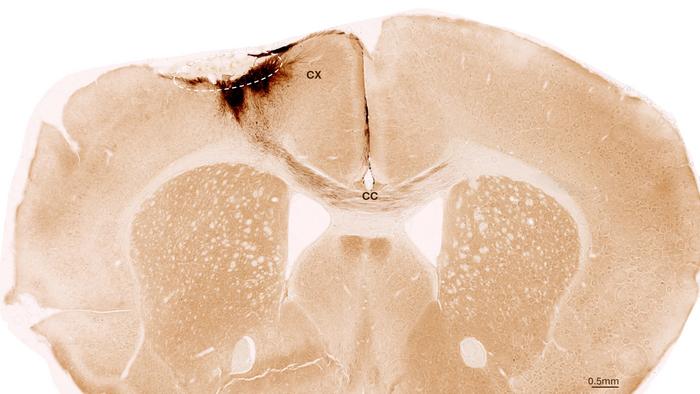

This image shows a coronal section through the mouse brain after stroke and neural stem cell transplantation. The dashed circle indicates the stroke area. The neurite projections of the transplanted human cells are stained in dark brown. Neurites extend locally into the cortex (CX) but also via the corpus callosum (CC) into the other brain hemisphere.

One week after stroke induction, the research team transplanted neural stem cells into the injured brain region and observed subsequent developments using a variety of imaging and biochemical methods. “We found that the stem cells survived for the full analysis period of five weeks and that most of them transformed into neurons, which actually even communicated with the already existing brain cells,” Tackenberg says.